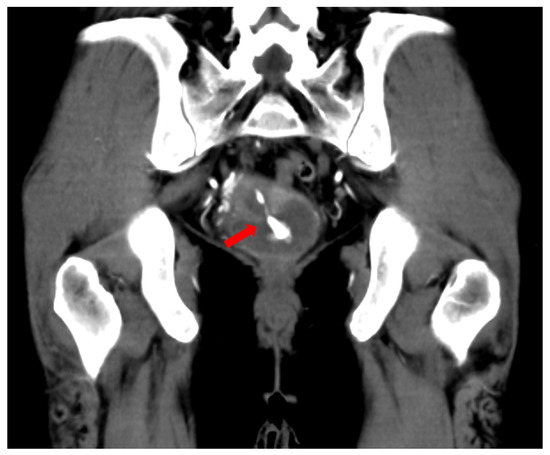

2. Case Presentation

| 6 | The present case | 40 | Nothing | Pain, hypotension, vaginal bleeding | Same day of OR | CT | Right pudendal artery | Gelfoam |